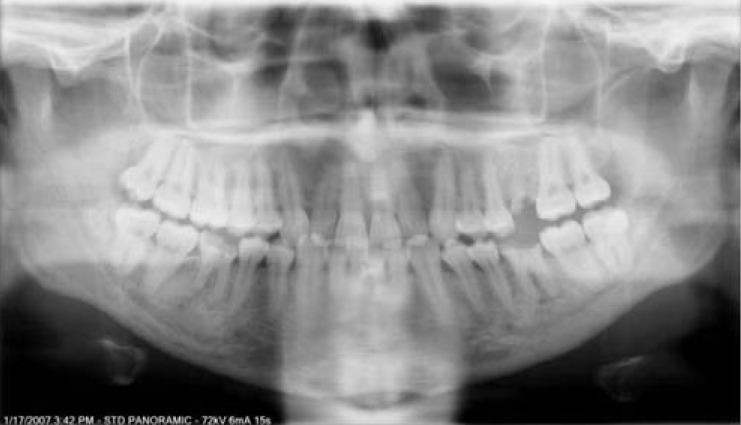

The panoramic image shows a flat or inverted smile line. The hard palate is superimposed over the maxillary roots.

Chin tipped too far up - reverse smile line